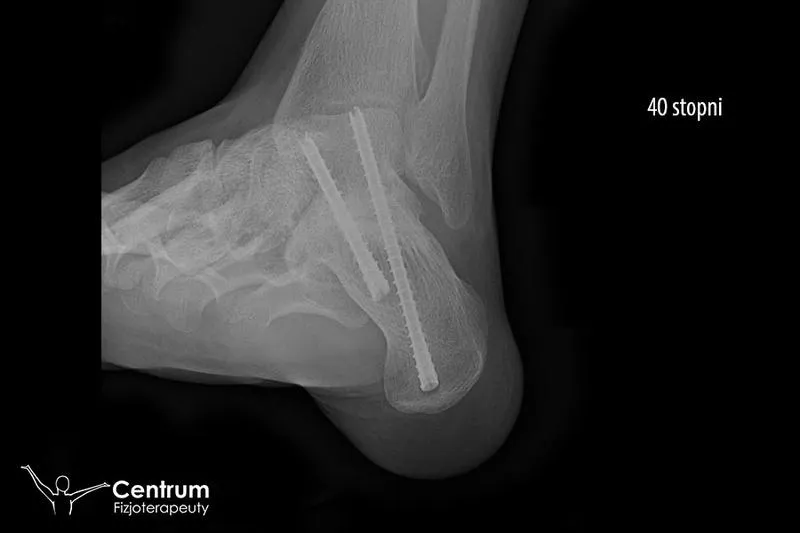

Cały proces zaczyna się od diagnostyki – trzeba ustalić, czy mamy do czynienia tylko z skręceniem, czy może ze złamaniem. Skręcenie można określić jako 'łagodne' doznanie, ponieważ po kilku tygodniach wracamy do aktywności. Natomiast złamanie? To znacznie poważniejsza sprawa, co może frustrować wszystkich. I nawet jeśli w gabinecie fizjoterapeuty brzmi zabawnie, pamiętaj, że będą wymagać od Ciebie regularnych ćwiczeń! Im więcej wysiłku i systematyczności, tym szybciej staniesz na nogi, z nadzieją, że nie zrobisz 'świństwa' z innym stawem!